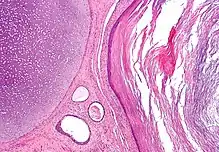

Dermoid cyst

A dermoid cyst is a mature cystic teratoma containing hair (sometimes very abundant) and other structures characteristic of normal skin and other tissues derived from the ectoderm. The term is most often applied to teratoma on the skull sutures and in the ovaries of females.

A mature teratoma is a grade 0 teratoma. They are highly variable in form and histology, and may be solid, cystic, or a combination of the two. A mature teratoma often contains several different types of tissue such as skin, muscle, and bone. Skin may surround a cyst and grow abundant hair (see dermoid cyst). Mature teratomas generally are benign, with 0.17-2% of mature cystic teratomas becoming malignant.[16]